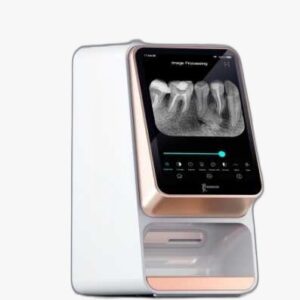

سنسور آر وی جی کداک RVG 142

سنسور پیشرفته با کاربردی آسان میباشد. ثبت تصاویر به کمک این سنسور به راحتی پوزیشندهی، اکسپوز اشعه و رویت تصویر است. در چند ثانیه تصویر ثبت شده قابل مشاهده بوده و زمان انتظار متخصص و بیمار به حداقل میرسد.

در این سنسور هیچگونه جعبهی کنترلی وجود نداشته و نیازی نیست آر وی جی را برای آمادهسازی به ابزار خاصی مجهز نمود. در حقیقت سنسورآر وی جی 142 همیشه آمادهی تصویربرداری است.

در قسمت خروجی کابل، برآمدگی پشت سنسور کم شده و اجازهی پوزیشندهی راحتتری در دهان بیمار میدهد. به تبع راحتی بیمار نیز تضمین شده خواهد بود. کابل این آر وی جی، ظریف، انعطافپذیر و قابل حمل میباشد. از طرف دیگر، این سنسور کاملا ضد آب بوده و امکان زدودن آلودگیها و بالا بردن ایمنی و بهداشت وجود خواهد داشت.

شناساگر دوز این سنسور، حداقل و حداکثر دوز تابش را مشخص نموده و به ار وی جی این توانایی را میدهد که تنظیمات تابش اشعه را مجددا اصلاح نماید.

در طراحی جدید سنسور آر وی جی کداک RVG 142، حدود ۵۰٪ از تعداد سیمها کاهش یافته ولی مابقی آنها برای دوام بیشتر تقویت شدهاند. کابل سنسور به نوبهی خود مقاومتر و انعطافپذیرتر شده و در برابر سختیها و کششها استحکام بیشتری دارد.

به دنبال دسترسی آسان به اطلاعات، در نرمافزار از برنامهی TWAIN استفاده شده است که مسلما برای کار با دیگر نرمافزارهای مدیریت درمان دندانپزشکی گزینهی ایدهآلی خواهد بود.